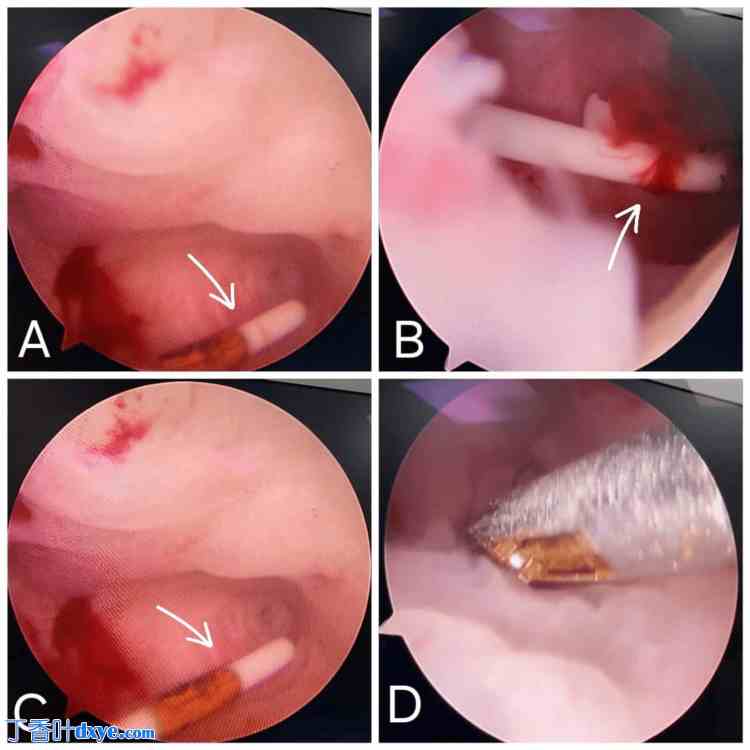

患者被告知需要进行宫腔镜宫内节育器取出术,并同意接受该手术。患者被送至手术室,并接受全身麻醉诱导。将手术宫腔镜轻轻放入宫腔,以便观察子宫内部。检查时,发现一个小的圆形息肉,如图 2 所示,该息肉覆盖在宫内节育器上。借助宫腔镜剪刀和双极电刀,仔细切除息肉。双极电刀可以进行选择性凝固和切割,从而避免术中出血。息肉完全切除后,用宫腔镜钳轻轻夹住宫内节育器 (IUD),如图 3 所示从子宫中拉出。整个手术过程约需 30 分钟。

图 2. 宫腔镜图像显示,A、B 和 C 图中可见小息肉遮挡宫内节育器 (IUD),D 图中显示使用宫腔镜剪刀进行切除。IUD 以白色箭头标记。